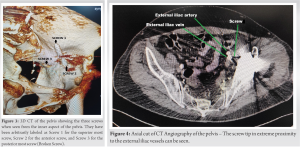

Acetabular bone loss was classified by Paprosky classification as Type 3A that is, superior and lateral migration ≥3 cm with intact medial support (Kohler’s line). To assess the proximity of these screws with the intrapelvic vasculature, a computed tomographic (CT) angiography of the pelvis with the lower limb was performed which, to our surprise, revealed one screw tip being interposed between the external iliac artery and vein (Fig. 4 and 5) and a catastrophic vascular injury waiting to happen.

Normal blood flow was noted through these vessels without any evidence of pseudoaneurysm formation. Long-standing symptoms led us to believe that there will be adhesions all around the screw, entangling the surrounding vascular structure. After a detailed discussion with the patient, an early intervention was planned in two stages. Revision surgeries are extensive with longer surgical duration, more blood loss, and a prolonged rehabilitation period. This case, in particular, was more extensive as it required two approaches, one for releasing adhesions around the screw and freeing the vessels and the second for prosthesis removal and definitive surgery.